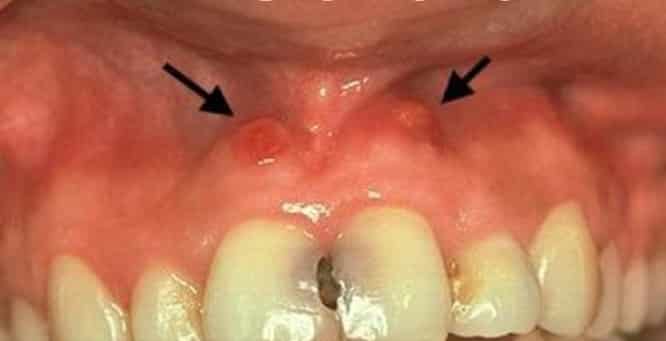

Если зуб под пломбой чешется и болит в течение нескольких дней или недель, это может быть нормальной реакцией или указывать на ошибку врача. В случае отека и опухания десны, необходимо срочно обратиться к стоматологу, так как это может быть признаком гнойного воспаления. Если не получить лечение, гной может образовать свищ и привести к отпусканию боли. Однако, спасти зуб возможно только при немедленном обращении к специалисту, так как неразрешенное гнойное воспаление может привести к серьезным осложнениям, таким как менингит. То же самое относится к развитию периодонтита и флюса в зубе с плохо запломбированными каналами. Хотя современные методы позволяют быстро лечить эти проблемы, повторное вмешательство может вызвать невралгию и боль при надавливании. Иногда болезненность может быть связана с аллергией на используемый материал, и только врач-стоматолог может определить причину и предложить соответствующее лечение. Обычно ошибку можно исправить, и зуб может быть спасен. В редких случаях, при длительной задержке обращения к врачу, может потребоваться удаление зуба и установка импланта или протеза.